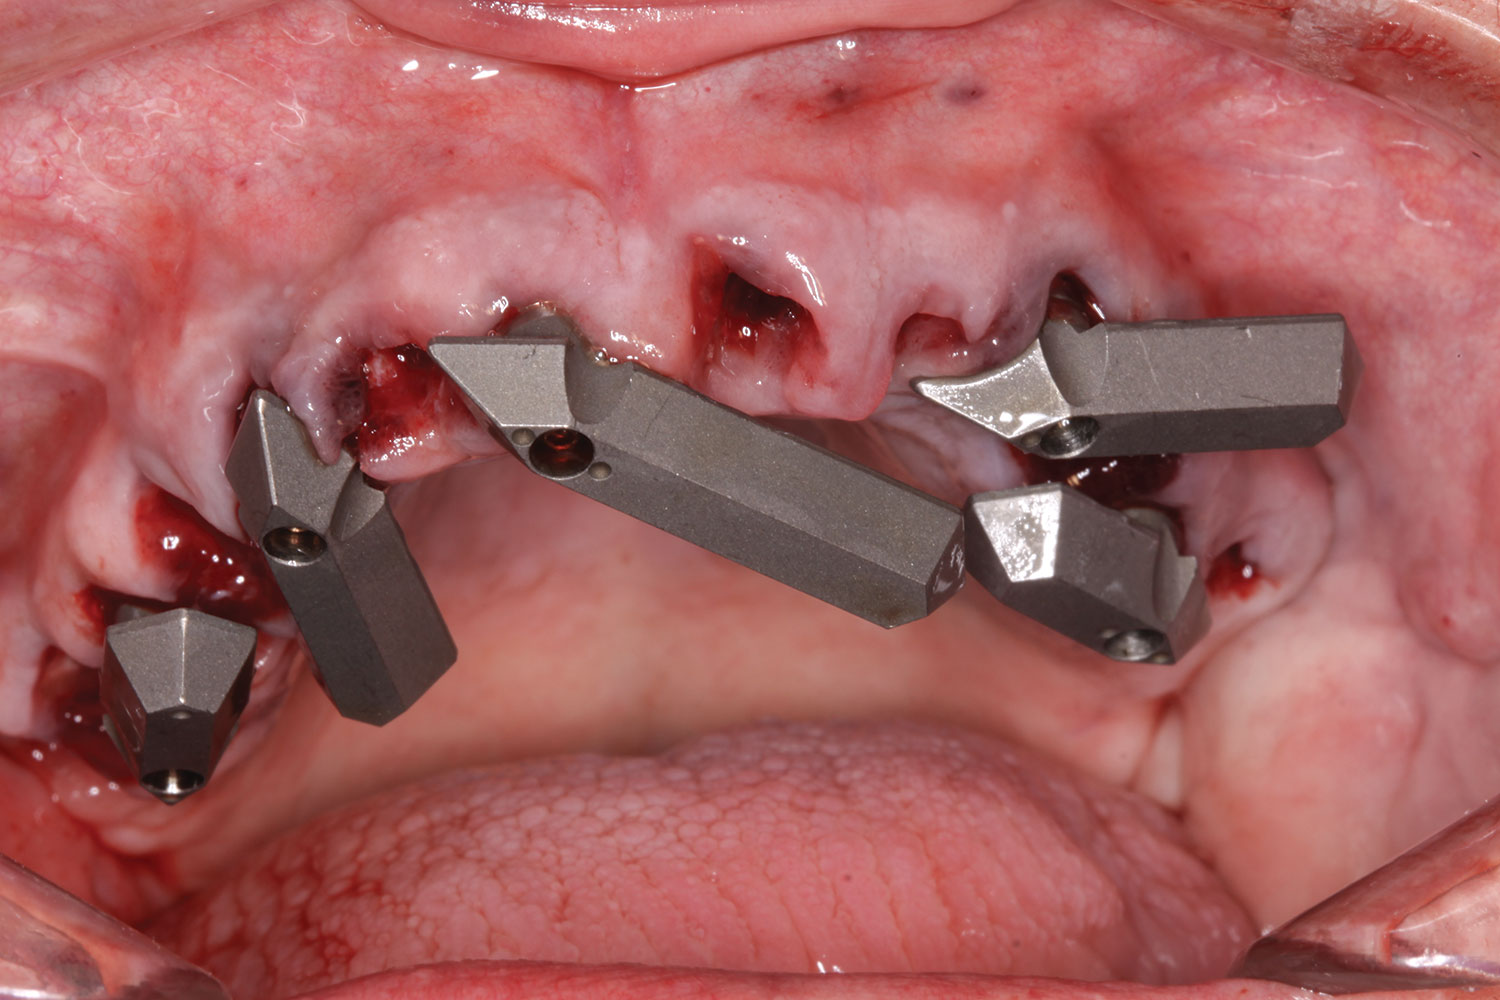

Scan gauges were then attached to the multi-unit abutments on the remaining implants so that all the implants were now in place with scan gauges (Figure 4). A scan was taken to capture all of the implants and surrounding soft tissue. The scanning protocol calls for scanning left to right, and then a separate scan right to left. These files were then sent electronically to the proprietary web portal.

Fig 4. Extractions completed; all implants, multi-unit abutments, and scan gauges in place.

Figure 4